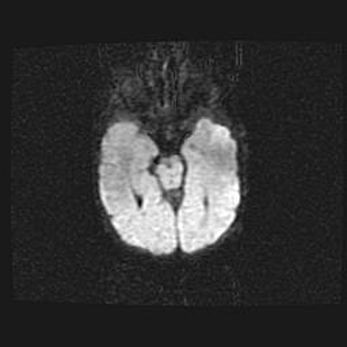

Множественные кисты обоих полушарий головного мозга, наибольшая из них в правой затылочной области. Ассиметричная атрофическая гидроцефалия.

Возраст: 7 месяцев

Вес: 5660 г

Пол: мужской

Окружность головы: 41,5 см

Срок гестации: 28-29 недель

Кисты головного мозга развиваются в результате многоочаговых некрозов вещества мозга и возникают вследствие перенесенной перинатальной инфекции, менингитов, энцефалитов, асфиксии, родовой травмы, расстройств мозгового кровообращения различного генеза. Образованию кист в веществе головного мозга плодов и новорожденных способствуют такие факторы, как высокое содержание в нем воды, недостаточная (или отсутствие) миелинизация и слабая астроглиальная реакция на повреждение.

Кисты могут сочетаться с гидроцефалией и другими поражениями головного мозга.